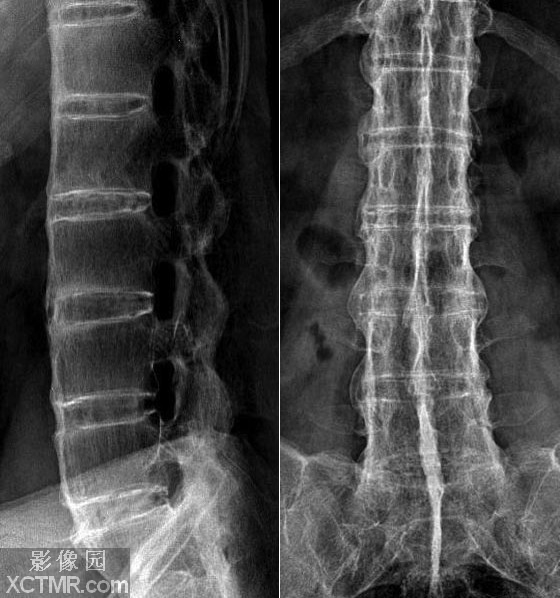

这个疾病的病情进展是十分缓慢的,早期也很难被发现或者检查到是否患病,但是他给患者带来的痛苦却是持续的长期的的,我们一定不能忽视他的危害。下面就是 贵阳风湿病中医院 专家介绍的强直性脊柱炎。 强直性脊柱炎不容我们忽视 在患病之后之后,全身很多关...[详细] 2015-05-27

这个疾病是非常的常见的,在疾病发生之后,身体的脊柱以及中轴骨骼还有身体的四肢都会因为疾病的原因受到不同程度的伤害,而且一般年龄不大的年轻人更加容易被疾病影响,为了让大家能够更加的重视这个疾病, 贵阳强直性脊柱炎医院 专家将为大家分析一下有什...[详细] 2015-05-21

疾病是否严重,对身体有多大的危害是每个人关注的地方,强直虽然非常的高发但是意外的是人们对这个疾病的认知却异常的少,患病后人们的心理上以及身体上面都会承受非常大的摧残,就这个问题 贵阳风湿病中医院 的专家特别整理出来了有哪些危害,这里分享给...[详细] 2015-05-19

有些时候,我们看到了有许多人背部是变形的,其实他们在生活中很不方便的,承受着自己的生活压力还有别人异样的目光。他们变成这个样子,其实是因为强直,大家还不清楚,下面就 贵阳风湿病中医院 带大家来看看导致背部变形的强直性脊柱炎的原因。 为什么强直...[详细] 2015-05-11

为了生活拼了命的人们,却忘记了身体才是本钱,越来越少的考虑到自己的身体情况,现在人们患得病也是五花八门,强直是这些疾病中危害相当大的一种,而且患强直性脊柱炎的数量也是逐年递增,这里 贵阳强直性脊柱炎医院 就给大家介绍一下这个病的危害都有什么...[详细] 2015-04-30

这个疾病是一种典型的和自身的免疫能力有一定关系,在很大程度上影响着我们的日常生活,许多人会问强直的危险性大?事实上,专家说,强直是一种危害较大的两种疾病,严重的可能会导致损坏,具体的 贵阳治疗强直性脊柱炎较好的医院 会向你介绍强直性脊柱炎:...[详细] 2015-04-27